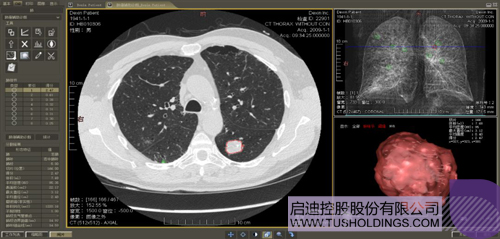

数字肺产品肺癌计算机辅助诊断

医疗影像智能分析是指运用人工智能技术、计算机视觉技术以及计算几何技术对医疗影像进行自动分析,帮助医生定位病症、分析、跟踪病情,并通过量化数据辅助医生做出诊断,目前其旗舰产品“数字肺”已经覆盖多种肺部疾病的早期检测、诊断、跟踪、术前规划等完整的医疗流程。在临床实践中,超过80%的医疗数据来自医疗影像,这些影像数据通常需要专业医生进行解读,工作的重复性高、效率偏低。如果能够运用智能影像分析技术,同时结合临床表现以及既往病例进行全面分析,那么就可以大幅度提升影像诊断效率和准确性,让专业医生的宝贵时间集中在复杂病情的诊断和治疗等环节。

肺动脉栓塞辅助诊断